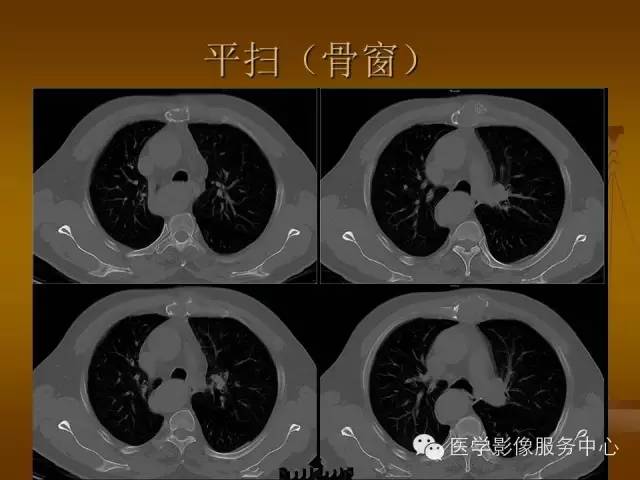

胸骨浆细胞骨髓瘤1例CT影像表现

特征性穿凿状、鼠咬状及蜂窝状骨质破坏,边缘清楚,骨质疏松,病理性骨折及软组织肿块等表现,骨质硬化及骨膜反应少见。

骨质破坏区完全为软组织取代,骨质膨胀,边界清楚,常突破骨皮质形成软组织肿块。